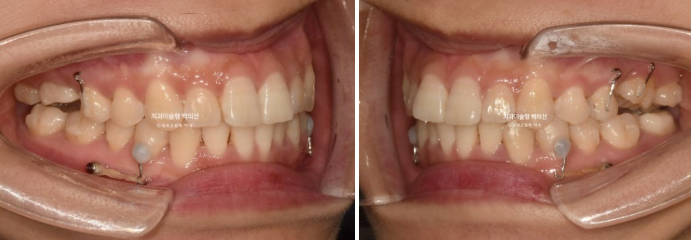

23.10

23년 10월 교정을 위해 온 30대 환자분입니다.

앞니는 뻗쳐있고 좌측 큰어금니 자리가 비어있습니다.

아래 앞니는 삐뚤하여 배열할 공간이 필요하고

위 첫번째 큰어금니 (제1대추치)가 한쪽은 발치되어있고 한쪽은 아직 발치는 안 했지만 발치진단이 나온 상황입니다.